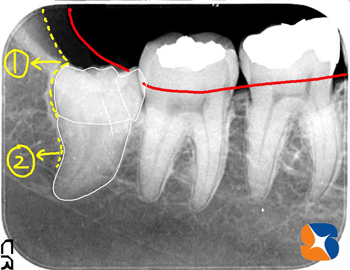

早速、レントゲン撮影をして確認。歯の頭はアゴ骨(=写真①=)が、歯の根は弯曲している(=写真②=)ため、親知らずが正位置まで放出できなかったと推測。

抜歯開始から30分後、無事に抜歯できました。予想通り、歯の頭の引っ掛りと、根の変形が、時間を費やした原因でした。

しかし、角度を変える見ると、歯の根の先端がかなり変形しています。この様に変形した親知らずを抜歯するには、特殊な器具やテクニックが必要となります。